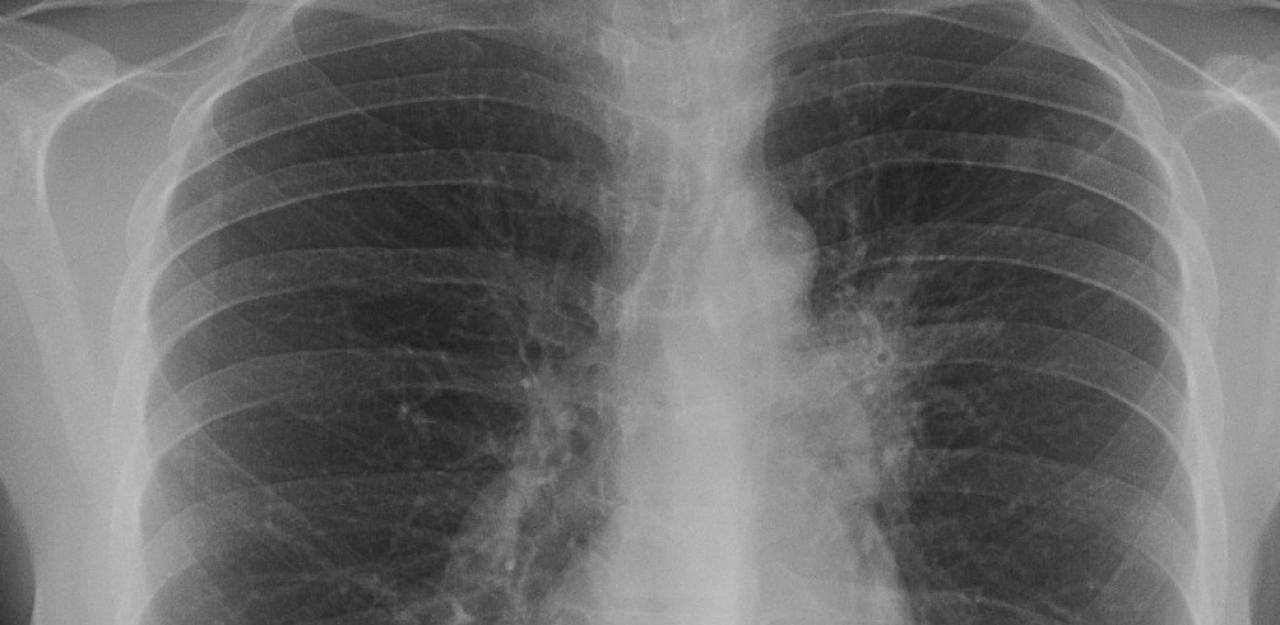

Tuberkulose-Fall in Purkersdorf: Jetzt kommt der nö. Röntgenbus.

Bild: Wikipedia (Symbol)